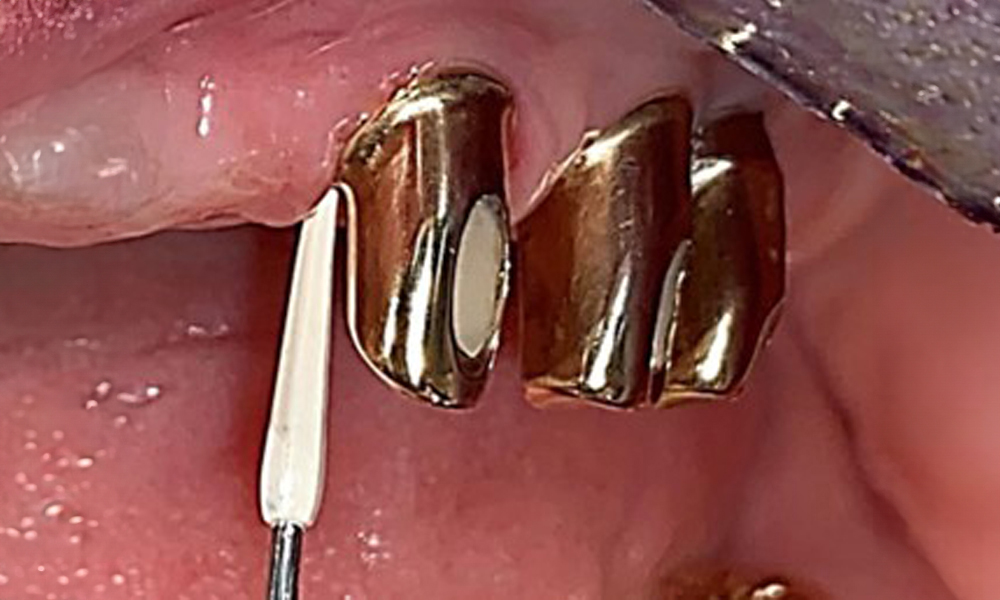

The dental findings are as follows: Combined removable implant and tooth-supported telescopic prostheses on implants 15, 13, 21, 23, 24, 25 and tooth 11 (Fig. 1, Fig. 2, Fig. 3). The patient was fitted with a fixed mandibular denture. Adequate bridges were present over 37 to 34 and 45 to 47 (Fig. 4), the crown margins were intact and there were no active caries. A composite filling with a marginal gap was present on tooth 43. There was mandibular gingival recession, exposing 1 to 3 mm of root surface. This also applies to 11.

Sonic/ultrasonic, or conventional manual instruments may be used to remove calculus and concretions present on the natural teeth (8). Titanium or plastic curettes (Fig. 10), or a plastic or PEEK attachment (Fig. 11) during ultrasonic treatment, should be used to remove mineralized plaque from implants to avoid damaging the implant surfaces.